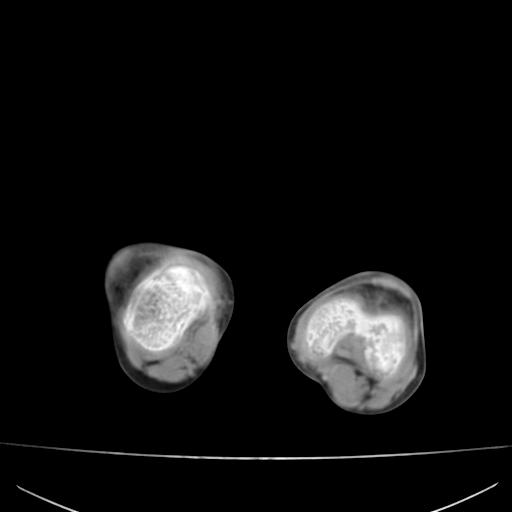

标题: PED0940:M12Y,左股骨下端酸痛畸形 [打印本页]

标题: PED0940:M12Y,左股骨下端酸痛畸形

12岁男孩,左膝关节肿痛8年,近月明显

内生骨软骨瘤?

血友性关节病?